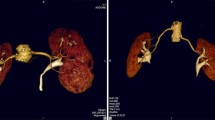

Preprocedural renal 4D-CTA and procedural DSA images from a patient with CCRCC with a single feeding artery. a Preprocedural coronal CT image shows CCRCC (14 mm) in the right kidney (black arrow). b Digital subtraction arteriography via microcatheter in segmental artery shows feeding artery (white arrowhead) and tumor stain (black dotted circle). The microcatheter was advanced to the position indicated by white arrowhead to embolize the feeding artery. c Axial CT image immediately after embolization shows that ethiodized oil is deposited throughout the tumor (white dotted circle). d‒f Coronal maximum intensity projection images of the 4th (d), 10th (e), and 11th (f) phases (delays 21.3, 33.9, and 36.0 s, respectively) of 4D-CTA show various degrees of renal artery branches. The 4th phase corresponds to that where the difference in contrast enhancement is the largest between renal artery and cortex in this patient, whereas renal artery enhancement is maximal in the 10th phase. Peripheral branches are most obvious in the 4th phase. g Coronal image of the 4th phase shows the corresponding feeding artery in renal parenchyma (white arrowhead). 4D-CTA four-dimensional computed tomography angiography, CCRCC clear cell renal cell carcinoma, DSA digital subtraction arteriography